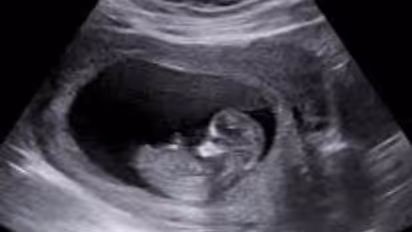

കുഞ്ഞിന്റെ ചലനവും അംഗവൈകല്യവും അറിയാൻ കഴിയുന്ന ഒബ്സ്റ്റട്രിക് സോണോഗ്രഫി അനോമലി എന്ന സ്കാൻ എടുത്തതാണെന്നും പരാതിക്കാരി അറിയിച്ചു. എന്നിട്ടും ഡോക്ടർമാർ വിവരം പറഞ്ഞില്ല. പ്രസവിച്ചപ്പോൾ കുഞ്ഞിന് നിരവധി അംഗവൈകല്യങ്ങൾ ഉണ്ടായിരുന്നുവെന്നും ഡോക്ടർമാർക്കെതിരെ ചികിത്സാപിഴവിന് കേസെടുക്കണമെന്നും പരാതിക്കാരി ആവശ്യപ്പെട്ടു.